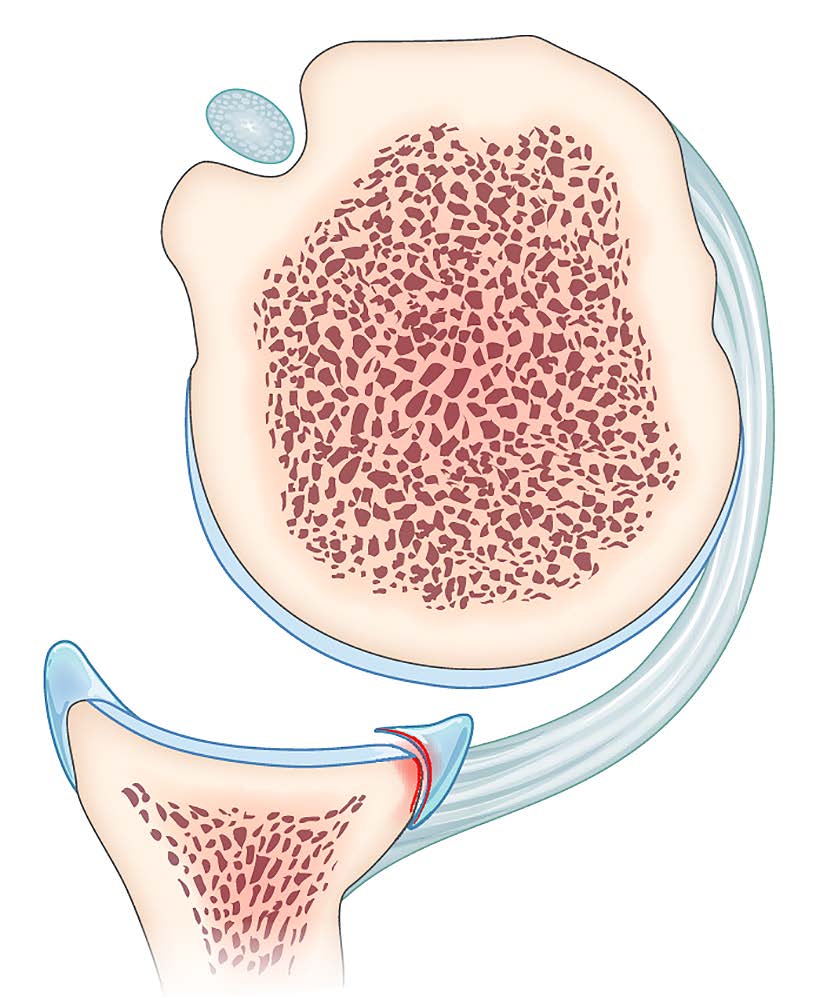

Mise au point Y a-t-il encore des indications à combler les encoches de Malgaigne sous arthroscopie ? , Claire Bastard Hôpitaux Universitaires Henri Mondor, AP-HP, Créteil, France , Geoffroy Nourissat Hôpital Saint-Antoine, 75012 Paris, France 🖂 gnourissat@wanadoo.fr N°289 - Décembre 2019 ● 11 min de lecture

Technique Le bankart augmenté , Aurore Blancheton Clinique Maussins-Nollet, 67 Rue de Romainville 75019, Paris, France , Geoffroy Nourissat Hôpital Saint-Antoine, 75012 Paris, France 🖂 gnourissat@wanadoo.fr N°289 - Décembre 2019 ● 7 min de lecture